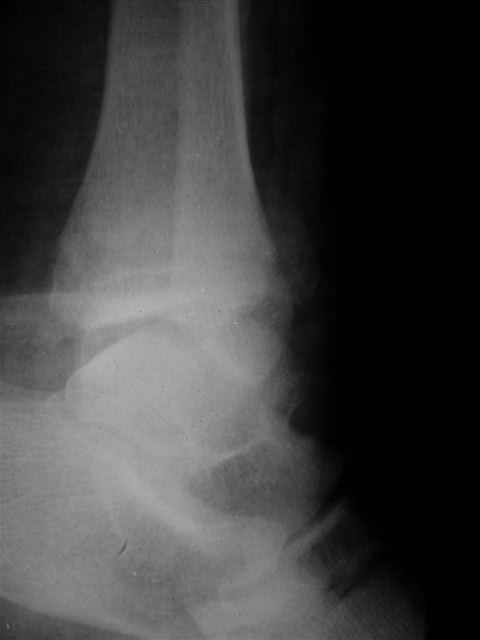

А можно,пожалуйста, более конкретно про повреждение голеностопного сустава?

В первом письме я упомянул о закрытом повреждении правого голеностопного сустава, эверсионно-пронационный механизм травмы - перелом внутренней лодыжки( поперечный, на уровне суставной щели) и отрывной перелом бугорка Chaput. После обработки открытых переломов бедра и большеберцовой кости в эту же сессию перелом внутренней лодыжки фиксировал двумя расходящимися спицами, бугорок Chaput двумя тягловыми винтами 3,5 мм. Раны заживают благополучно. Учитывая повреждение наружной группы мышц, активное разгибание в голеностопном суставе ограничено. Пассивная + пассивно-активная мобилизация голеностопного сустава с физиотерапевтом.

Каких-либо вопросов по лечению травмы голеностопного сустава у меня не возникло,поэтому о дальнейших деталях лечения я не упоминал.

(Если вы заинтересовались, то Рг граммы представлю)

Уважаемый Иван,

Я предупреждал, что ничего сверхъестественного. Каюсь, что одна из спиц прошла несколько дальше, чем нужно было, но главное - перелом стабилизирован и больной работает суставом в полном объёме, несмотря на представленную раннее травму коленного сустава.